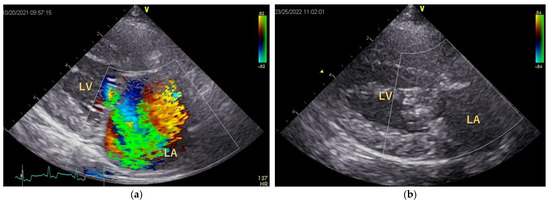

The postoperative follow-up period was 162 ± 126 days. After MODEL surgery, five dogs showed no cough, and the remaining dog had a cough that was 1/10th of its preoperative level. The preoperative intensity of systolic murmur was Grade 5 in five dogs and Grade 4 in one dog; however, it disappeared postoperatively in five dogs, while the remaining dog still had a Grade 2 murmur. MR disappeared or was markedly reduced (Figure 4). Within 1 week of MODEL surgery, three of the six dogs had thrombi in the posterior wall of the left atrium (2/3) or on the artificial CT (1), although these disappeared over time, and there were no clinical signs of thrombosis.

Figure 4. Color Doppler echocardiography. (a) Preoperative parasternal four-chamber view showing large turbulence mosaic patterns from the left ventricle to the left atrium, indicating the presence of severe MR. (b) Postoperative parasternal four-chamber view shows the disappearance of MR and reduction in the left atrial size. LA: left atrium; LV: left ventricle.